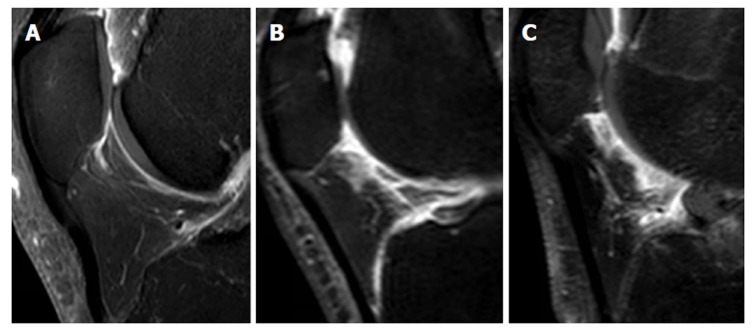

Synovial membrane score (SM score): The contrast effects and signal intensity changes along the posterior surface of the Hoffa’s fat pad on a single sagittal slice through the central patellofemoral groove were used to semiquantitatively grade the synovitis. The score was based on the contrast effects and signal intensity changes[17] on sagittal T1CE; low-signal areas on sagittal PD; and high-signal areas on sagittal PD-FS. The score was graded on a four-point scale as grade 0 for lack of enhancement or signal change; grade 1 for the presence of a linear contrast effect or signal change on the posterior fat pad synovium; grade 2 for the presence of a nodular contrast effect or signal change on the posterior fat pad and/or mild exudation of the fat pad on T1CE; and grade 3 for gross a nodular contrast effect or signal change on the posterior fat pad and/or severe exudation of the fat pad on T1CE, as seen on the sagittal plane at the center of the patella (Figure 2).

Figure 2.

Grading of the Synovial membrane score. A: Grade1 is defined as linear thickening of the posterior Hoffa’s fat pad’s synovium; B: Grade 2 is defined as mild exudation and signal change in the posterior Hoffa’s fat pad; C: Grade 3 is defined as gross nodular thickening of the posterior Hoffa’s fat pad’s synovium.